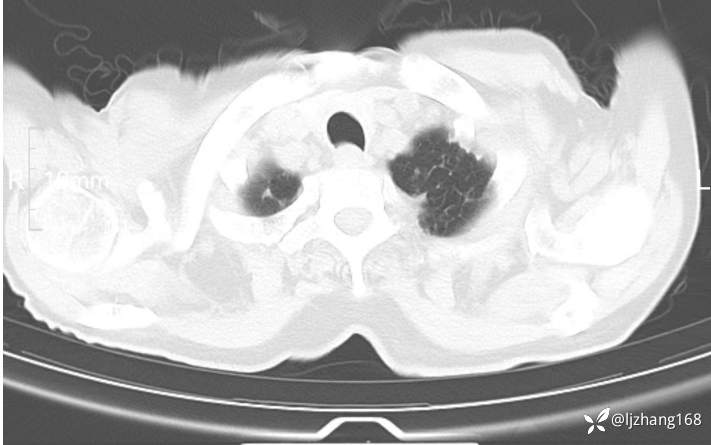

辅助检查:胸部CT:双肺肺气肿,间质性病变,血气分析:PH 7.413, PCO2 29.2mmHg, PO2,81.8mmHg,乳酸 3.3mmol/1,剩余碱-4.0mmol/1,HC03 18.8mmol/1。全血超敏C反应蛋白:超敏C反应蛋白 135.60 mg/L、 白细胞 14x19^9/L,中性粒细胞11.6x10^9/L。